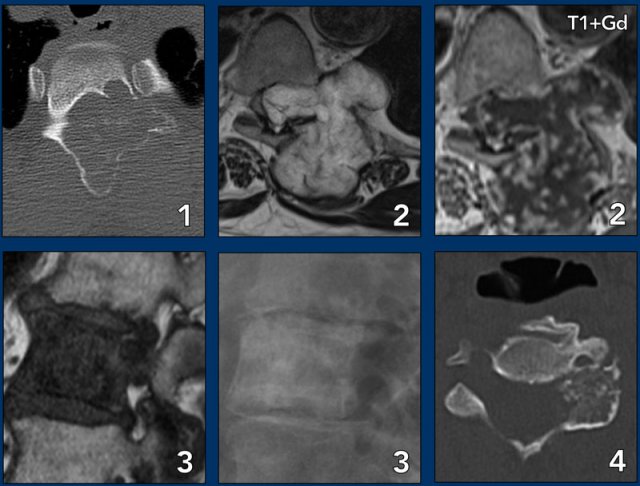

Spine lesions

Here some typical examples of bone tumors in the spine.

1. Hemangioma.

2. Metastasis.

3. Multiple myeloma.

4. Plasmocytoma: vertebra plana.

This 'Mini Brain' appearance of plasmacytoma in the spine is sufficiently pathognomonic to obviate biopsy (9).

More examples

1. ABC

2. Chondrosarcoma

3. Metastasis of breast cancer

4. Osteoblastoma